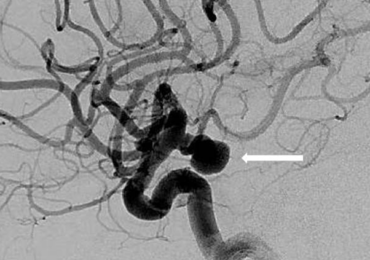

Figure 3. Anterior 2D angiographic view of a cerebral aneurysm (white arrow) located at the left carotid artery bifurcation (left). The cerebral aneurysm after one coil has been placed inside the aneurysm (middle) and the final image (right) after the coiling has been completed demonstrating aneurysm occlusion.